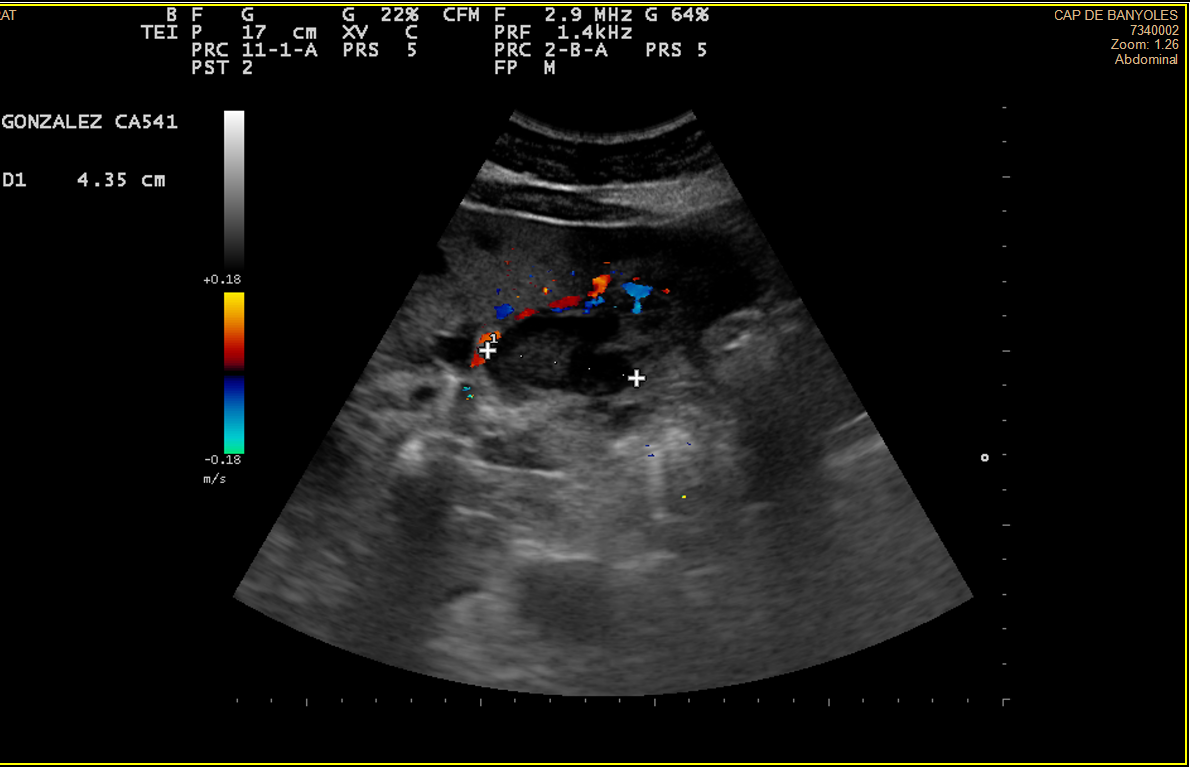

Alteración difusa de la ecoestructura hepática, presentando múltiples imágenes hipoecoicas, de diversos tamaños, resaltando una lesión en lóbulo hepático derecho de 3cm, tabicada y con ecos en su interior, con componente vascular asociado. Vesícula de aspecto normal.

TAC Abdominal: Hemangiomatosis hepática difusa sobre hepatopatía esteatósica.